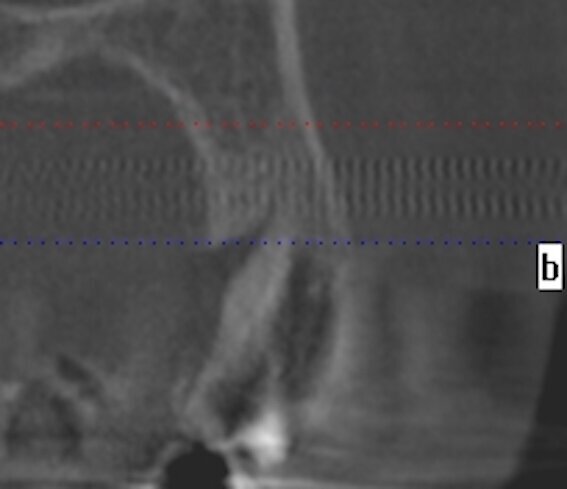

La cone beam rivela il mantenimento volumetrico del tessuto osseo periimplantare (Figg. 6a-6c). Questo case report evidenzia l’importanza della customizzazione delle cappette di guarigione per il mantenimento dei volumi dei tessuti perimplantari. La forma delle cappette di guarigione simili alle radici dei denti estratti avvitate sugli impianti post-estrattivi evitano il collasso volumetrico dei tessuti, guidando la guarigione dei tessuti perimplantari con il mantenenimento volumetrico dell’alveolo. Con questa metodica si riduce il numero delle procedure tradizionali eseguite per il trattamento implanto protesico negli impianti post-estrattivi. Si evita la riapertura del lembo gengivale, le varie fasi della ribasatura del provvisorio per il condizionamento gengivale, riducendo i tempi e i costi. Con questa procedura si lavora in modo conservativo, si velocizzano i tempi di esecuzione del flusso di lavoro mantenendo inalterati i parametri morfologici e volumetrici dei tessuti periimplantari. E tutto questo flusso di lavoro è possibile effettuarlo direttamente alla poltrona diminuendo i costi e il tempo per il paziente.

Fig. 1b - La sezione alla Cone beam.